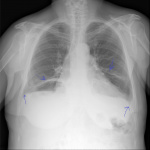

Пациента 70 лет. Две недели назад была температура , перенесла на ногах , что на снимке?

Поствоспалительные фиброзные измененя в легких, более похоже на последствия перенесенной пневмонии?

Хорошо бы свриться с архивом. Фиброз, как вариант, возражений не вызывает.

год назад не было фиброзных изменений . Есть ли признаки гидроторакса , или все-таки синусы свободны, затемнений нет?

Синусы свободны, диафрагма уплощена. Справа не исключу реактивные субсегментарные ателектазы. Контроль в динамике.

С учетом того, что " 2 недели назад была температура" и " год назад не было фиброзных изменений" можно предположить в лучшем случае течение нижнедолевой 10сегмент пневмонии ( генез?) м.б. с некоторым уменьшением об' ема, в худшем случае обтурацию сегментарного бронха. О двухнедельном фиброзе говорить рано. Согласен " контроль в динамике".

Обозвал бы это дисковидными ателектазами.

А болевого синдром нет, со стороны органов грудной клетки или верхнего этажа брюшной полости? Правда, картина похожа на дисковидные ателектазы.